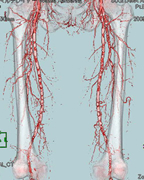

- 大動脈狭窄 【写真】

- 高位大動脈閉塞(Leriche synd) 【写真】

- 腸骨動脈完全閉塞(右) 【写真】

- 腸骨動脈狭窄 【写真】

- 浅大腿動脈狭窄 【写真】

- 浅大腿動脈閉塞 【写真】

- 3枝閉塞 【写真】

- 脛骨腓骨動脈幹(peroneal trunk) 【写真】

- 後脛骨動脈(posterior tibial artery) 【写真】

- 腎動脈 【写真】

- 鎖骨下動脈 【写真】

考え方としては、早期であるほど2の血管内手術のみで治る可能性が高いと考えてよいでしょう。現在の末梢動脈に対する血管内手術の適応は、大動脈・腸骨動脈領域から膝下動脈、さらに足関節から足趾にまで及びます。しかし、それぞれの治療法には当然ながら適応があります。このためしばしば従来からの手術との組み合わせであるハイブリッド手術が必要になりますが、血管内呪術の関与する割合は8~9割にも及んでいます。